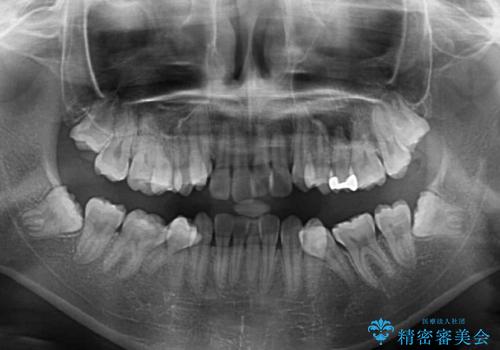

- 前歯の叢生と八重歯を気にして来院された患者様です。

叢生が強く、奥歯の咬合も左右差が大きかったため、上下左右4本を抜歯して、ワイヤー矯正を行うこととしました。